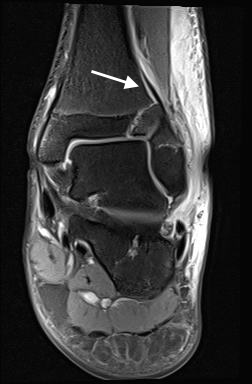

Osteochondrale Verletzungen

Osteochondrale Verletzungen können infolge eines Distorsionstraumas beobachtet werden (Taluskantenfraktur), teilweise lässt sich auch kein Trauma eruieren. Der es sich bei osteochondralen Verletzungen um keine Arthrose handelt, ist gerade bei Schmerzfreiheit ein defensives Vorgehen angezeigt. Bei offenen Wachstumsfugen kann eine osteochondrale Verletzung unter konservativer Therapie ausheilen.

Eine retrograde Anbohrung ist indiziert, wenn sich im MRT Verlauf eine zunehmende Sklerosierung im Randbereich der Läsion zeigt bei intakter Knorpeloberfläche.

Instabile Knorpelareale werden arthroskopisch entfernt in Verbindung mit einer Mikrofrakturierung der subchondralen Knochenlamelle.